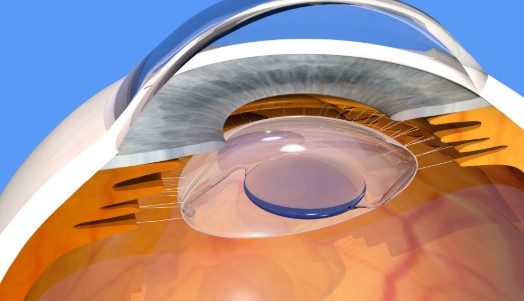

تحسين الرؤية لمسافة واحدة مع استقرار وأمان تام بعد العملية.

رؤية واضحة للمسافات القريبة والمتوسطة والبعيدة، وتقليل الحاجة للنظارات بعد العملية.